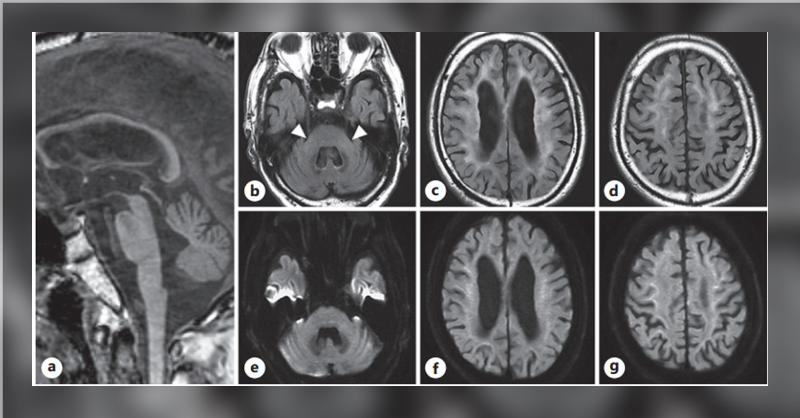

A 68-year-old man with an 8-year history of right arm postural tremor and cognitive decline was initially diagnosed with Parkinson's disease. Despite treatment with 400 mg/day of levodopa/carbidopa and 0.75 mg/day of pramipexole, there was no improvement. Zonisamide (25 mg/day) partially alleviated the tremor, prompting referral. Neurological exami